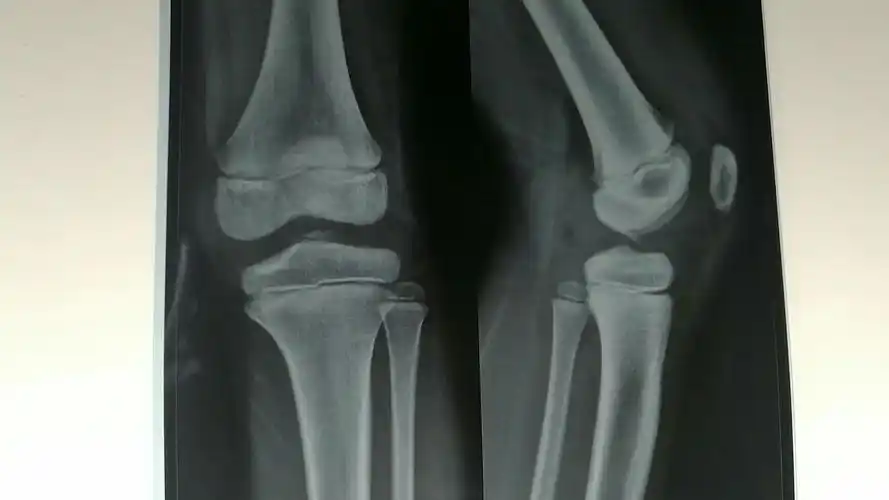

胫骨髁间嵴骨折一例

胫骨髁间棘骨折术前dr片!